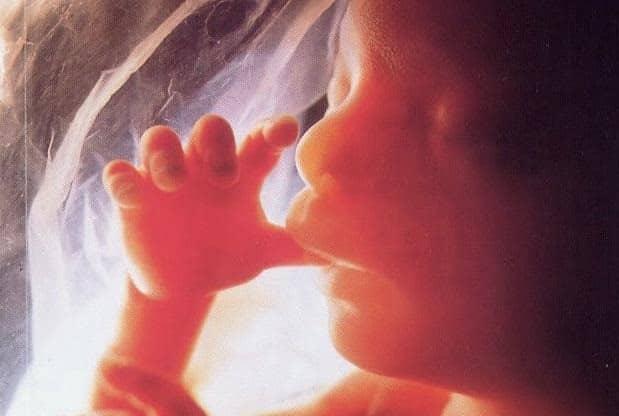

Nước ối là môi trường giúp thai nhi phát triển và được bảo vệ cho đến khi chào đời. Vì vậy, việc phát hiện sớm những bất thường về nước ối trong thai kỳ là vô cùng quan trọng. Trong đó, thiếu nước ối là một trong những vấn đề có thể gây nguy hiểm cho thai nhi. Tuy nhiên, hầu hết các mẹ bầu không biết nhiều hoặc không có khái niệm về tình trạng này.

Nước ối là chất dịch chứa đầy trong túi ối xung quanh bào thai đang phát triển trong tử cung của người mẹ và có những vai trò rất quan trọng như:

- Bảo vệ, che chở cho thai tránh những va chạm

- Ngăn không cho dây rốn bị chèn ép, vì nếu dây rốn bị nghẹt sẽ làm giảm cung cấp oxy cho thai nhi

- Giúp duy trì nhiệt độ ổn định của thai nhi trong tử cung

- Chống lại nhiễm trùng

- Cho phép thai nhi vận động được dễ dàng để cơ và xương phát triển đúng cách.

Trong 14 tuần đầu của thai kỳ, nước ối được tạo ra từ hệ tuần hoàn của mẹ bầu trong màng ối. Vào đầu tam cá nguyệt thứ 2, bé bắt đầu nuốt nước ối và bài tiết nó như nước tiểu, sau đó nuốt lại, tái lập đầy đủ lượng nước ối mỗi vài giờ. Điều này có nghĩa hầu hết phần nước ối là nước tiểu của thai nhi. Vì vậy, thai nhi cũng đóng một vai trò quan trọng trong việc giữ đúng thể tích dịch ối trong túi ối. Đôi khi, sự cân bằng này bị phá vỡ dẫn đến quá nhiều hoặc quá ít nước ối.